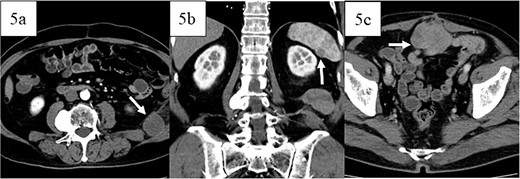

Postoperatively, the patient developed paralytic ileus, resolving with conservative treatment, and was discharged 21 days after surgery. Adjuvant therapy was not administered because the patient had a complete resection with clear margins. Twelve months later, retroperitoneal recurrence was noted (Fig. 5a), and doxorubicin was started. Sixteen months post-surgery, splenic metastasis was detected (Fig. 5b). After five cycles of doxorubicin, the patient had progressive disease but refused invasive treatment and received supportive care. Peritoneal dissemination was identified 27 months post-surgery on CT (Fig. 5c). The patient died 3 years and 2 months post-operation.

Images of contrast-enhanced computed tomography, contrast-enhanced computed tomography scan revealed recurrence in the retroperitoneum 12 months postoperatively (white arrow in 5a) and metastases in the spleen 16 months postoperatively (white arrow in 5b), and peritoneal dissemination (white arrow in 5c) 27 months postoperatively.